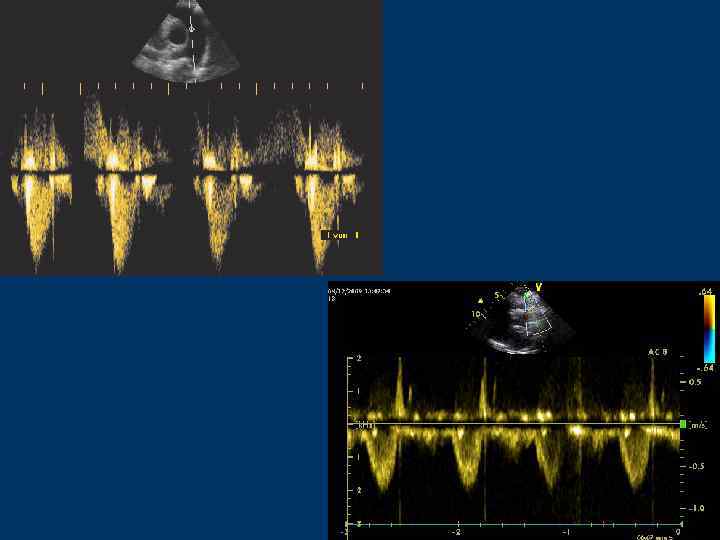

Импульсноволновой допплер (Pulsed wave, PW)

Контрольный объем (sample volume) – место исследования кровотока. Длина – 2 -20 мм.

Pulsed Wave Doppler

Pulsed Wave Doppler Достоинства метода: • Возможно регистрировать кровоток в любой камере сердца или магистральном сосуде • Регистрация потока на строго определенной глубине → точная локализация потока • Место исследования – контрольный объем

Pulsed Wave Doppler. Недостатки метода: • Предельная скорость, которую можно измерить, определяется пределом Найквиста → возможно искажение спектра (aliasing) • Невозможно зарегистрировать высокоскоростные потоки • Зависимость оценки спектра скоростей от угла между осью УЗ луча и направлением кровотока